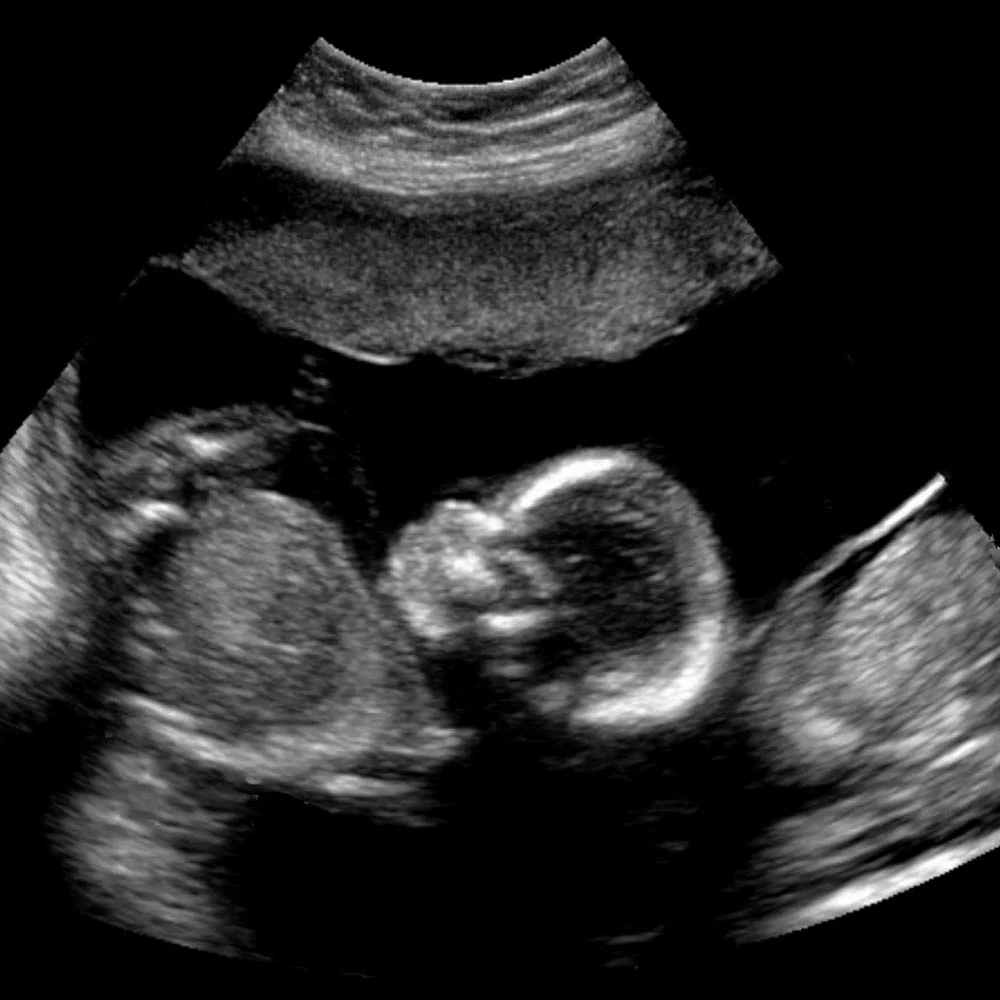

Неделя № 22

На 22 неделе размеры плода увеличиваются до 28 см, вес – до 450-500 грамм. Размеры головки становятся пропорциональны туловищу и конечностям. Ноги практически все время находятся в согнутом состоянии.

Полностью сформирован позвоночник плода: он имеет все позвонки, связки и суставы. Продолжается процесс укрепления костей.

Совершенствуется нервная система плода: головной мозг содержит уже все нервные клетки (нейроны) и имеет массу около 100 грамм. Ребенок начинает интересоваться своим телом: ощупывает свое лицо, руки, ноги, наклоняет голову, подносит пальцы ко рту.